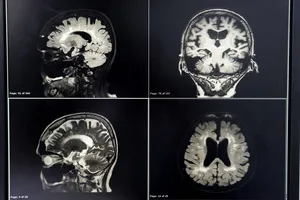

병원에서는 뇌 CT 또는 MRI 검사를 통해 뇌경색을 진단하고, 혈전용해제 투여 등 적절한 치료를 시행합니다.